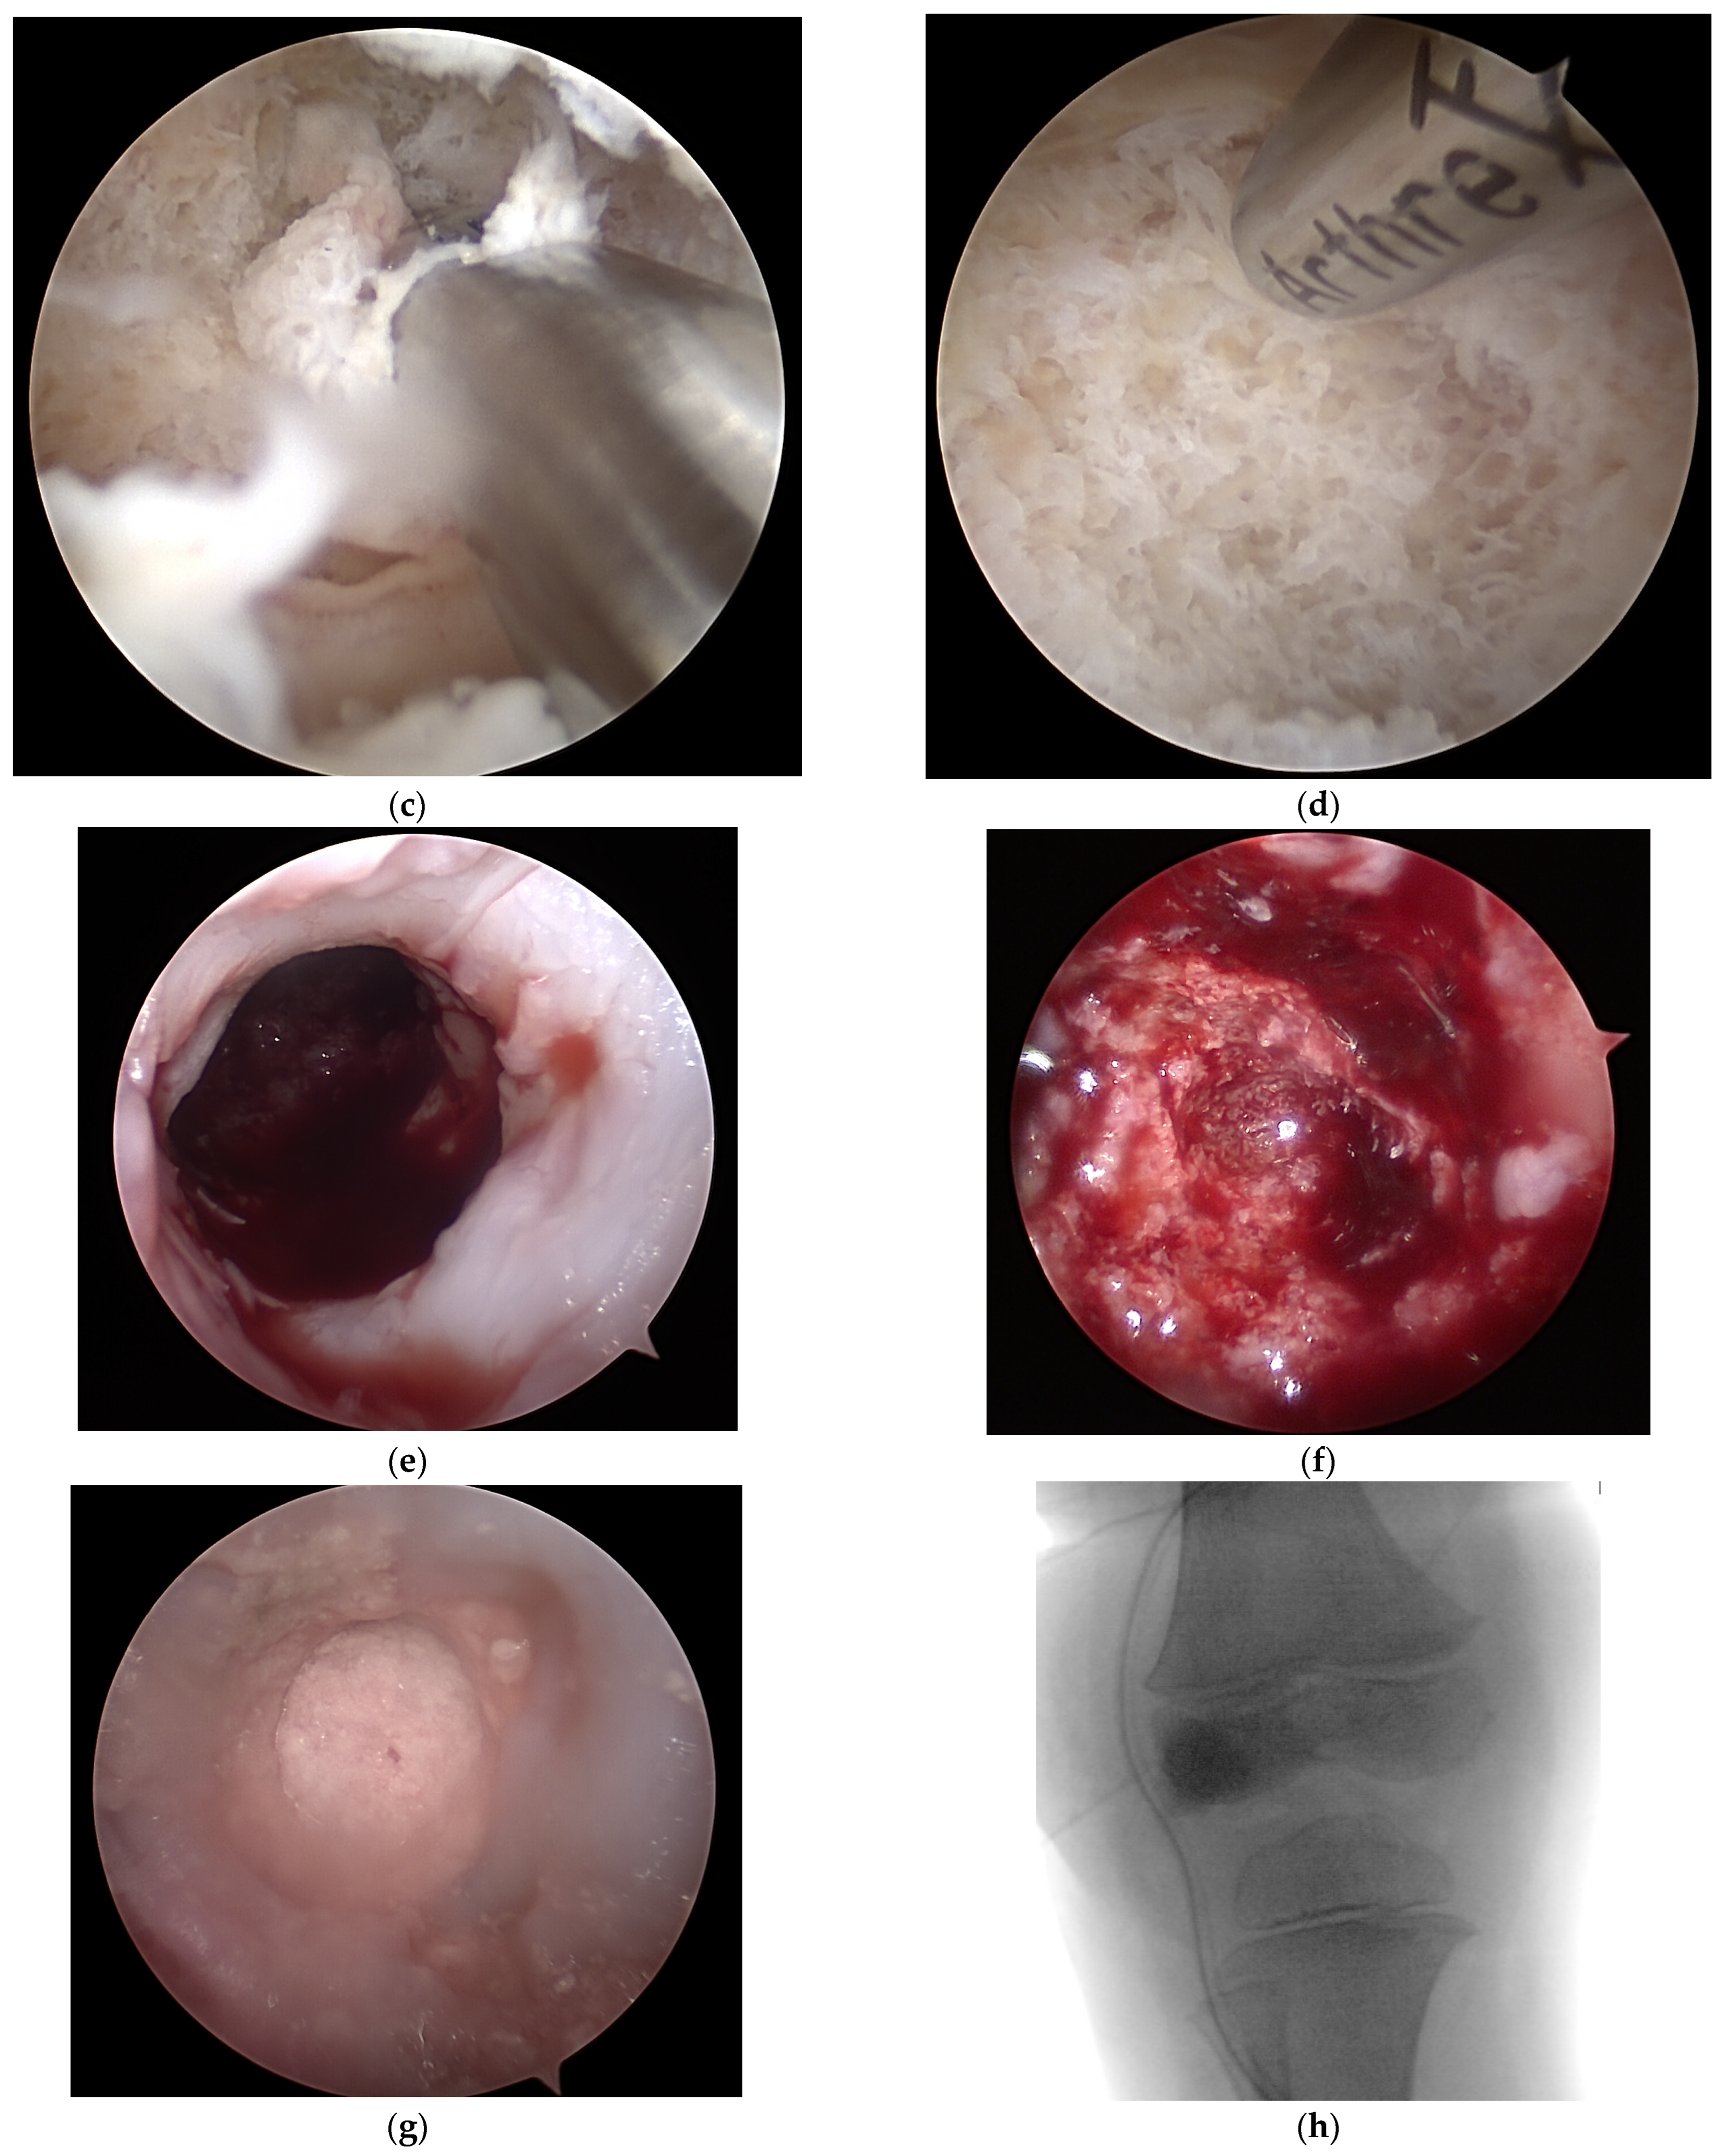

Surgical Management of an Osteomyelitis Associated Subchondral Bone Defect in the Pediatric Knee Based on Arthroscopy, “Ossoscopy” and Bone Grafting—A Case Report

2. Case Presentation